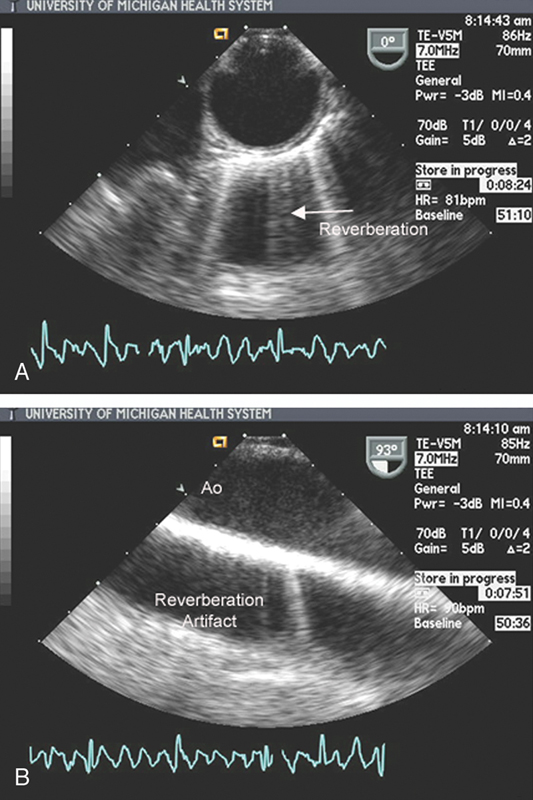

فحوصات تشخيصية لبعض امراض القلب والشرايين التاجية